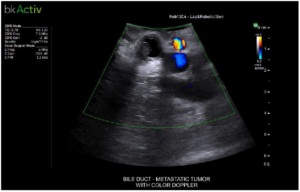

Bile Duct – Metastatic Tumor With Color Doppler

iUS uses color flow doppler to help differentiate between vessels and ducts and is overall effective at imaging difficult cases such as inflammation or fibrosis .1.4 - 6